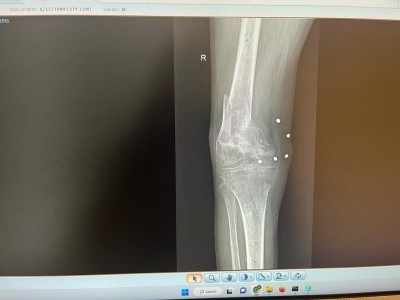

ORTOPEDIE-TRAUMATOLOGIE: Interventie chirurgicala de protezare segmentara a genunchiului la un pacient tanar cu fractura deschisa la nivelul genunchiului

La 7 luni de la accident s-a prezentat in serviciul nostru cu anchiloza marcata a genunchiului si defect osos sever la nivelul femurului distal.

"Defectul osos mare de la nivelul femurului distal impun o reconstructie a genunchiului cu endoproteza segmentara pentru defect femural mare pe care impreuna cu echipa mea (dr. COSTE REMUS, dr. DRAGHICIOIU HOREA, dr. MUBARAK FADOL, as. GAVRA MONICA) am efectuat-o in luna iunie 2022. Lipsa mare de os de la nivelul femurului distal am inlocuit-o cu un sistem GMRS Stryker.